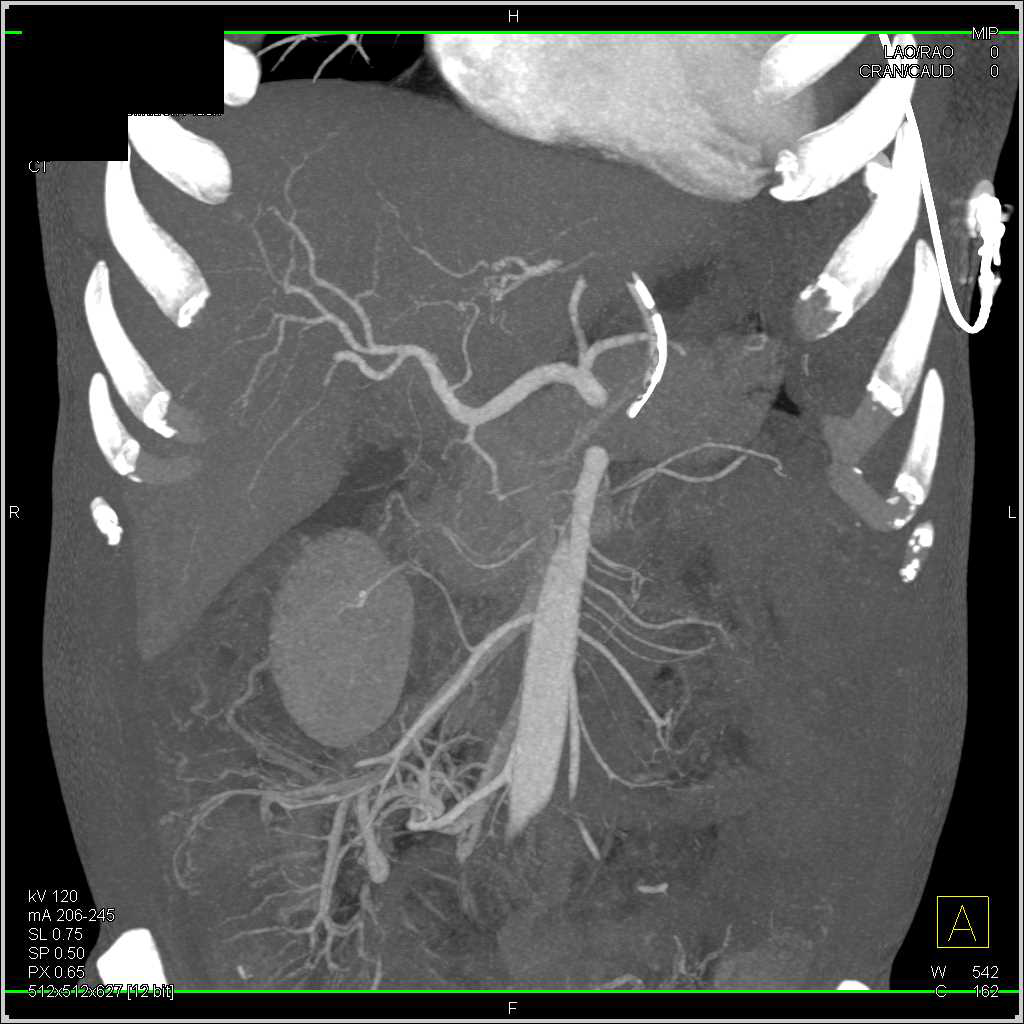

Small Bowel Obstruction (SBO) due to Adhesions